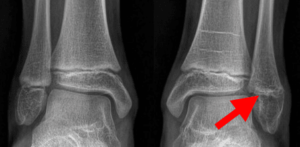

Understanding Ankle Fractures in Children

In children and adolescents, ankle fractures typically affect the tibia or fibula, often involving the growth plates—specialized areas of cartilage near the ends of long bones. Growth plates play a critical role in bone development, gradually hardening into solid bone as the child matures. However, because these growth plates are the last parts of the bones to solidify, they are particularly prone to injury and fractures.

As adolescents approach the end of their growth phase, growth plates begin to close and harden, making them susceptible to transitional fractures during this maturing stage. Two common types of transitional ankle fractures are triplane fractures and Tillaux fractures, which require specific treatment approaches depending on their severity and location (refer to the Treatment section for more details)